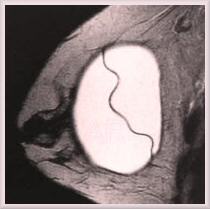

smooth-silicon1

A MR scan of a round, smooth walled, silicone gel implant in place within a  breast